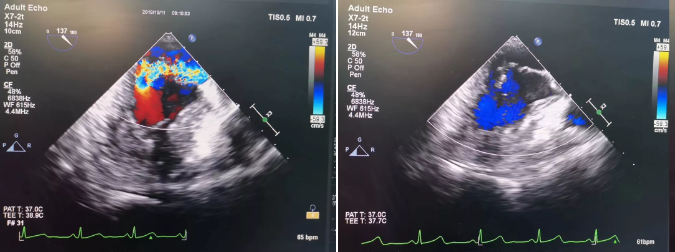

本次接受手术的患者是一位71岁女性,术前诊断为二尖瓣后叶瓣下腱索断裂并脱垂导致二尖瓣大量反流,由于不耐受外科手术,经导管进行的微创二尖瓣修复手术成为首选。术中,潘湘斌教授于患者第五肋间切开3-4cm小口,在单纯超声引导下植入人工腱索,器械操作仅耗时9分钟。术后超声即刻显示术前大量的二尖瓣反流基本消失,结构周直播会场响起了经久不衰的掌声。此例直播手术向结构周大会现场展示了MitralStitch®系统的安全性、有效性和便捷性,引起了与会专家的热烈反响。潘湘斌教授介绍,本例患者使用MitralStitch®系统成功进行二尖瓣解剖修复后,不仅使患者的心脏瓣膜功能得以恢复,临床症状得到改善,更保留了患者瓣膜自然解剖状态以及未来经导管进一步介入治疗的可能性。

术前、术后